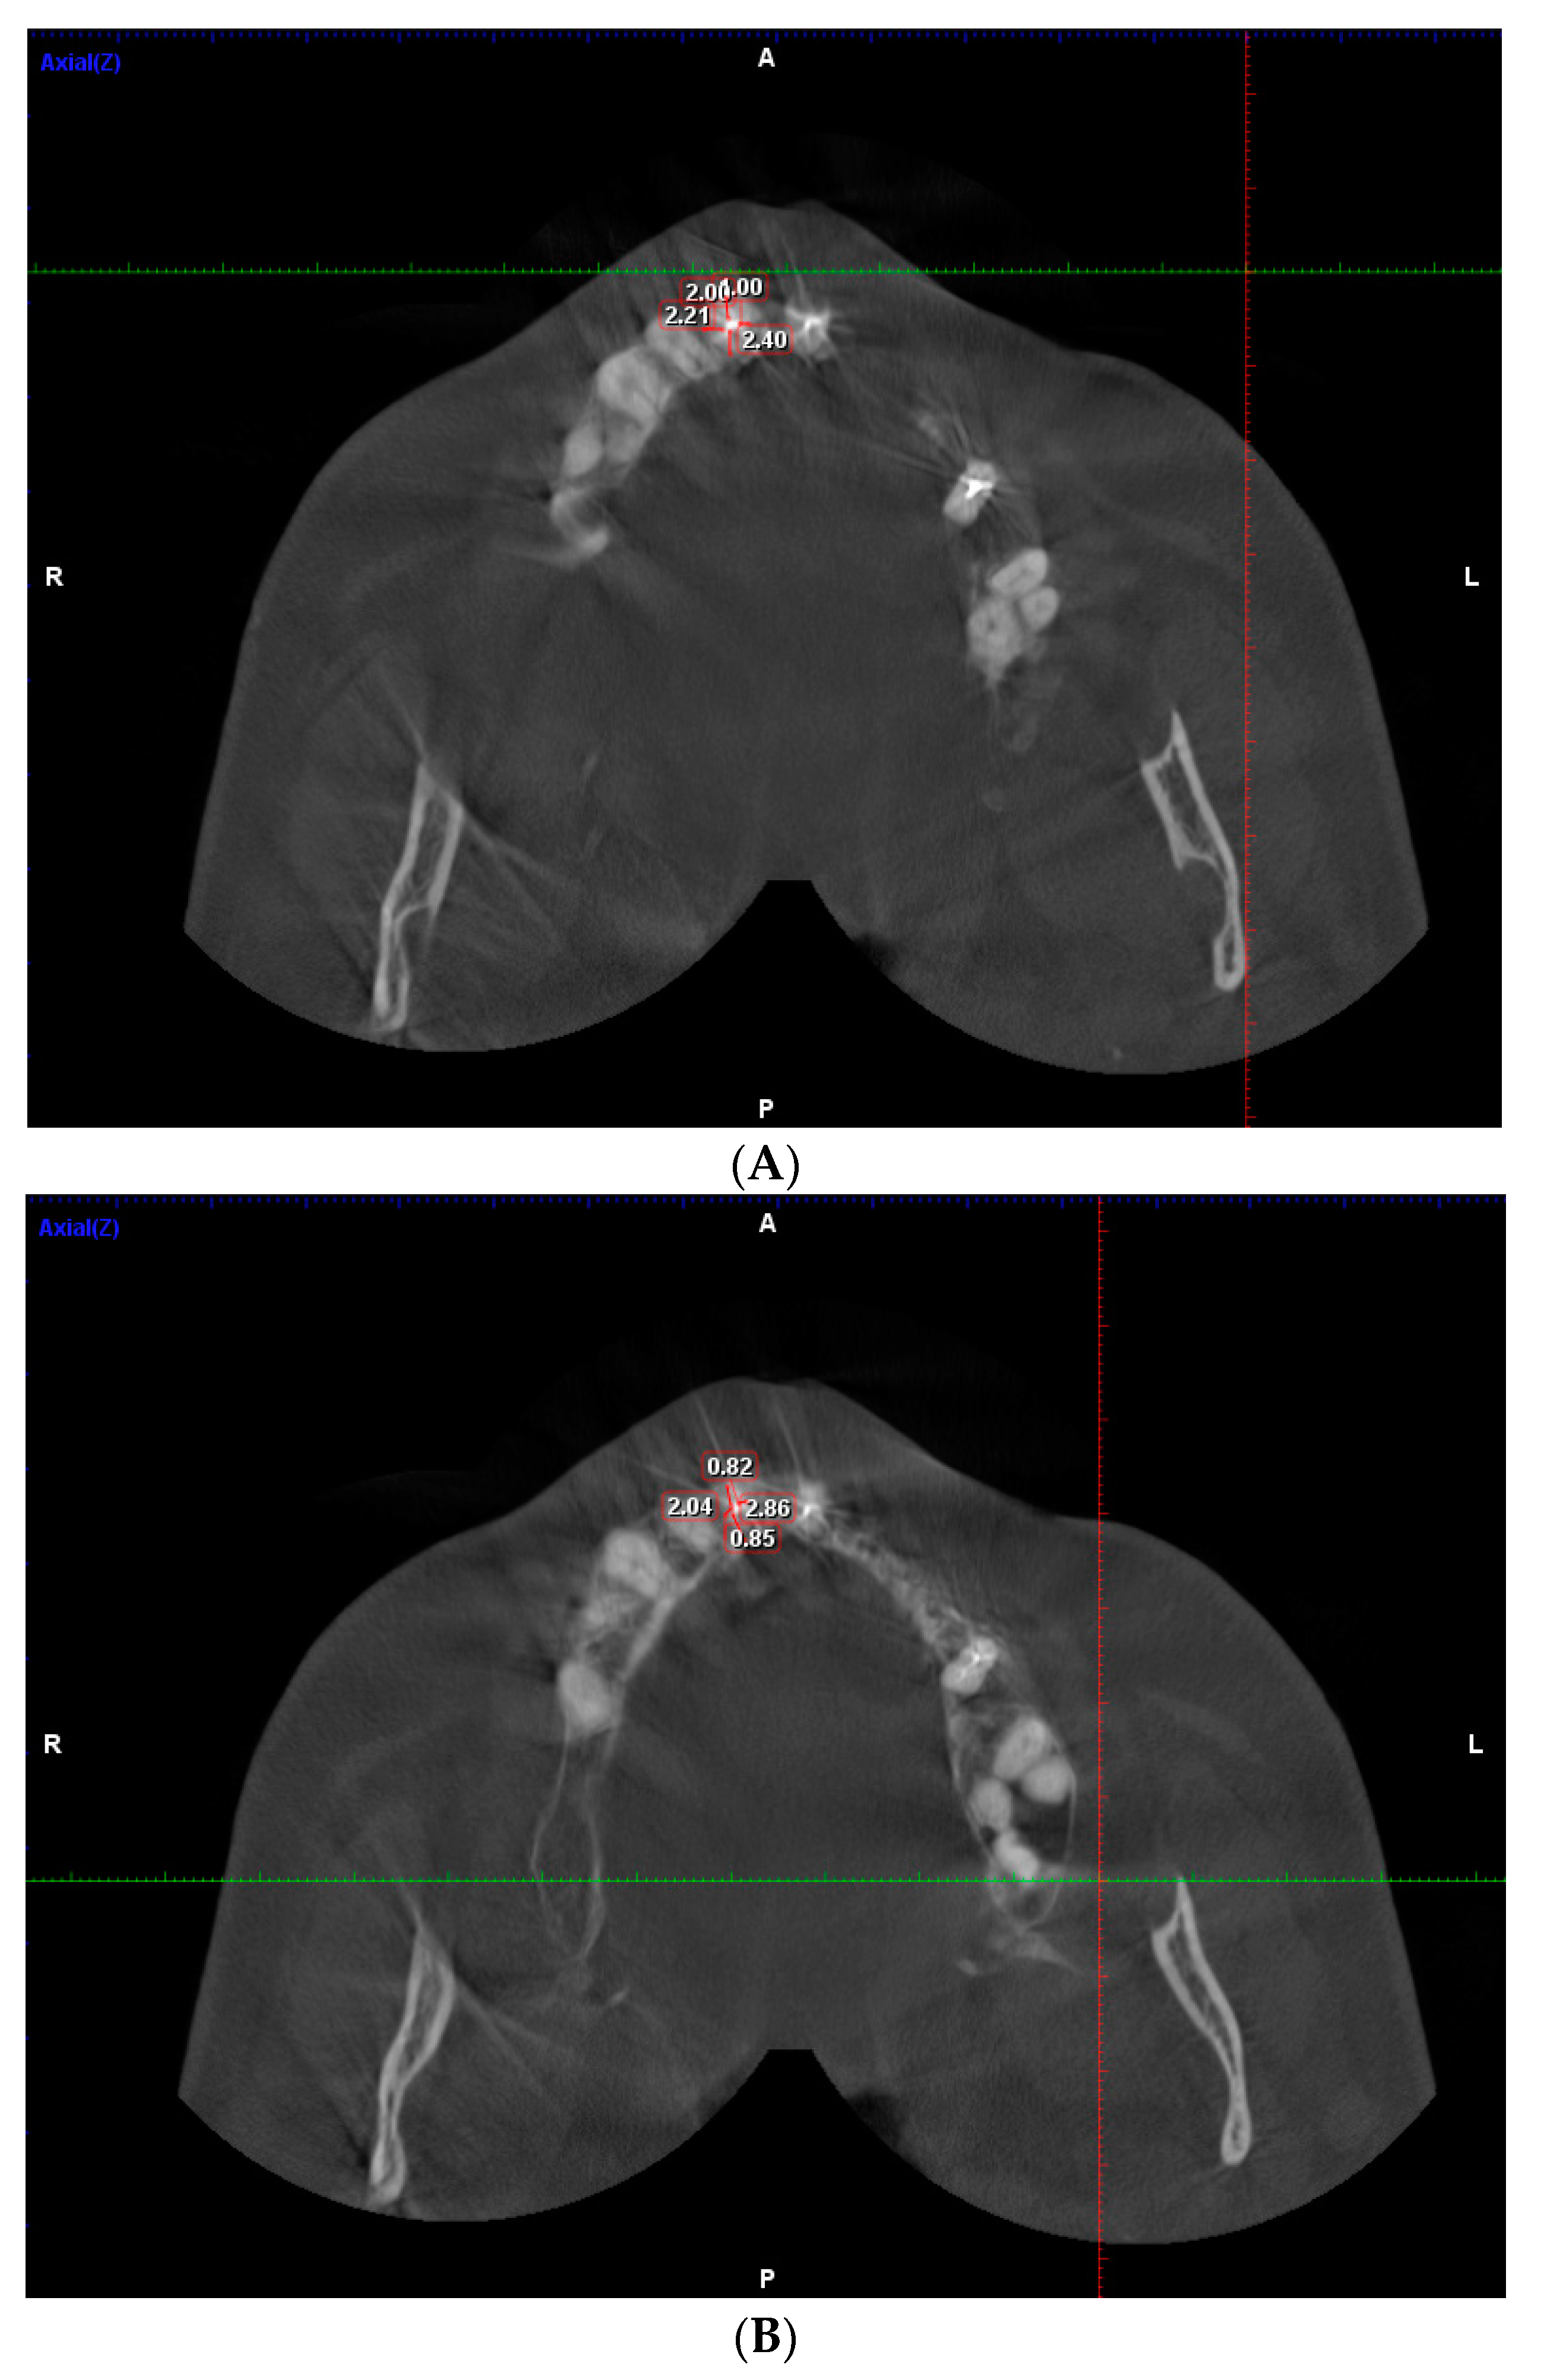

2. Materials and Methods

3.1. Measurment of DT of Maxillary Teeth

3.2. Measurment of DT Mandibular Teeth